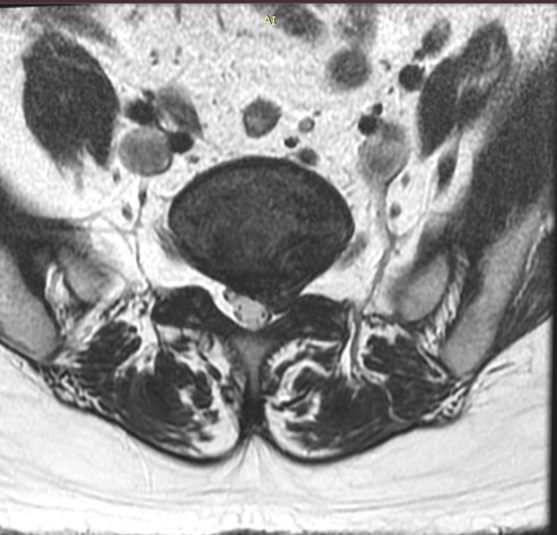

「ヘルニコアR」投与前のイメージ(左下)では髄核が後方に突出して神経を圧迫しているが、投与後(右下)では髄核のプロテオグリカンを選択的に分解するため、保水能を低下させる。これにより神経根の圧迫も低減されるのだ。